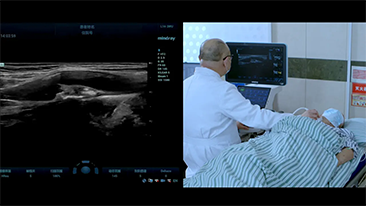

Mindray Resona-oplossingen voor algemene beeldvorming helpen clinici bij het realiseren van nauwkeurigere en effici?ntere diagnose- en behandelingsresultaten door middel van sondes voor aparte toepassingen en effici?nte klinische toepassingstools.

Inzichten

De medische omgeving van vandaag is complexer geworden, met een toenemend aantal moeilijke gevallen en meer werkdruk.